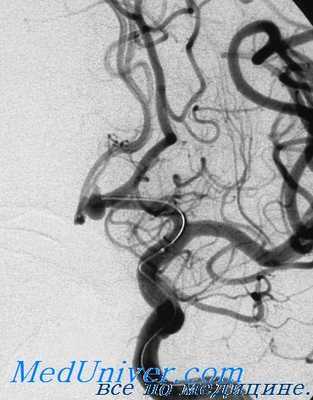

Все операции выполняли в плановом порядке, после комплексного обследования, в которое в обязательном порядке входили УЗДГ БЦА, МСКТ брахицефальных артерий или прямая ангиография, исследование функции сердца (ЭКГ, ЭхоКГ, коронарография).

Все операции выполняли в условиях комбинированного эндотрахеального наркоза с внутривенным потенцированием. Для оценки коллатерального кровотока из системы контралательной ВСА и вертебробазилярного бассейна и толерантности головного мозга к пережатию ВСА мы применяем транскраниальную допплерографию. Одеваем на голову пациенту шлем и на уровне височного окна датчиком 2 МГц лоцируем среднюю мозговую артерию (СМА) на стороне операции. Пробу с пережатием проводим в условиях управляемой артериальной гипертензии при АД 150—170 мм рт.ст. Снижение средней скорости кровотока в СМА на стороне операции более чем на 50% от исходного и/или исчезновение пульсирующего характера кровотока в ней служит показанием для применения временного ВПШ.